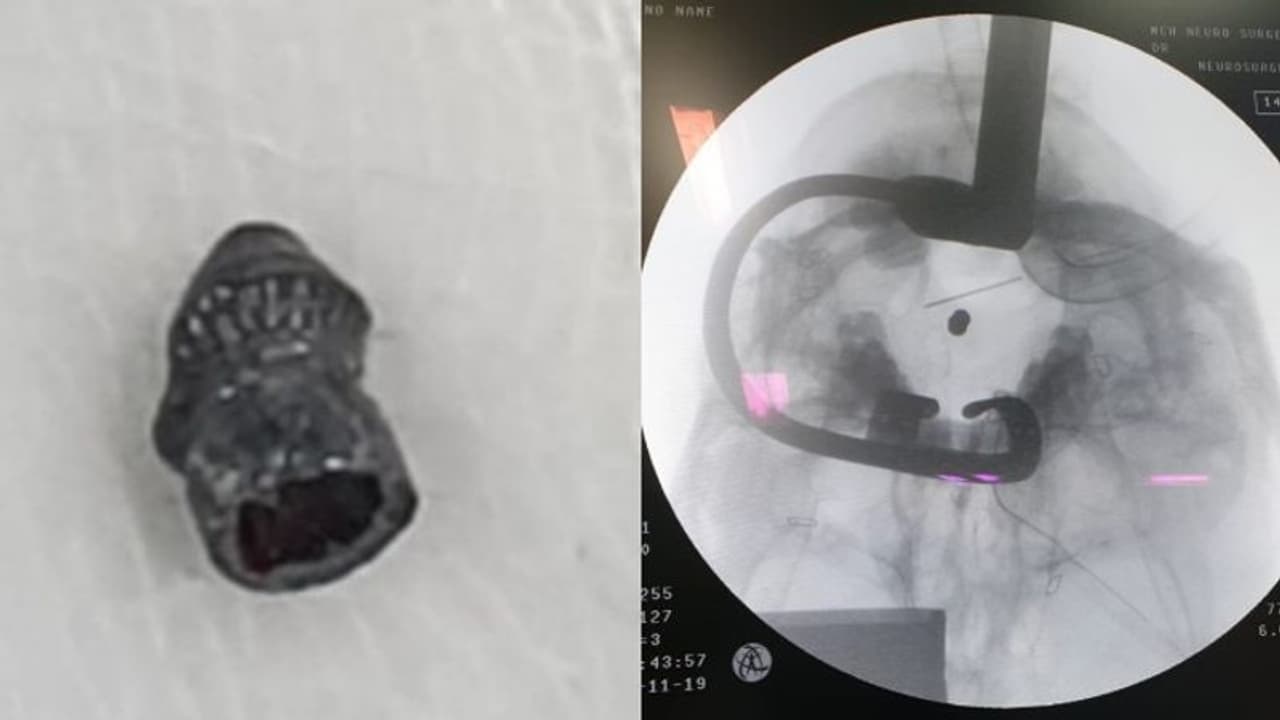

എയർഗൺ തുടച്ചു വൃത്തിയാക്കുന്നതിനിടെ വെടി പൊട്ടുകയും വെടിയുണ്ട വായിലൂടെ തുളച്ചുകയറി തലയോട്ടിയ്ക്കടിയിൽ മെഡുലയ്ക്ക് മുന്നിലായി തറച്ചു നില്ക്കുകയുമായിരുന്നു. ന്യൂറോ സർജറി വിഭാഗത്തിൽ പ്രവേശിപ്പിച്ച യുവാവിനെ അഡീഷണൽ പ്രൊഫസറും ആശുപത്രി സൂപ്രണ്ടുമായ ഡോ. എംഎസ് ഷർമ്മദിന്റെ നേതൃത്വത്തിൽ ശസ്ത്രക്രിയയ്ക്ക് വിധേയനാക്കുകയായിരുന്നു.

മൈക്രോസ്കോപ്പ്, സിആം എന്നീ ഉപകരണങ്ങളുടെ സഹായത്തോടെ വായിലൂടെ തന്നെ നടത്തിയ ശസ്ത്രക്രിയയിലൂടെ വെടിയുണ്ട പുറത്തെടുത്തു. മൂന്നര മണിക്കൂർ നീണ്ട ശസ്ത്രക്രിയയിൽ ന്യൂറോ സർജറി വിഭാഗത്തിലെ ഡോ. അഭിഷേക്, ഡോ. രാജ് എസ് ചന്ദ്രൻ, ഡോ. ദീപു, ഇ എൻ ടി വിഭാഗത്തിലെ ഡോ. നിഖില, ഡോ. മുബിൻ, ഡോ. ലെമിൻ, ഡോ. ഷാൻ, അനസ്തേഷ്യാ വിഭാഗത്തിലെ ഡോ. ഉഷാകുമാരി, ഡോ. ജയചന്ദ്രൻ, ഡോ. നരേഷ്, ഡോ. ഗായത്രി, ഡോ. രാഹുൽ, നേഴ്സുമാരായ ബ്ലെസി, സിന്ധു തീയേറ്റർ ടെക്നീഷ്യൻ ജിജി, സയന്റിഫിക് അസിസ്റ്റൻറ് റിസ് വി, തീയേറ്റർ അസിസ്റ്റന്റുമാരായ നിപിൻ, വിഷ്ണു എന്നിവർ ശസ്ത്രക്രിയയിൽ പങ്കാളികളായി.